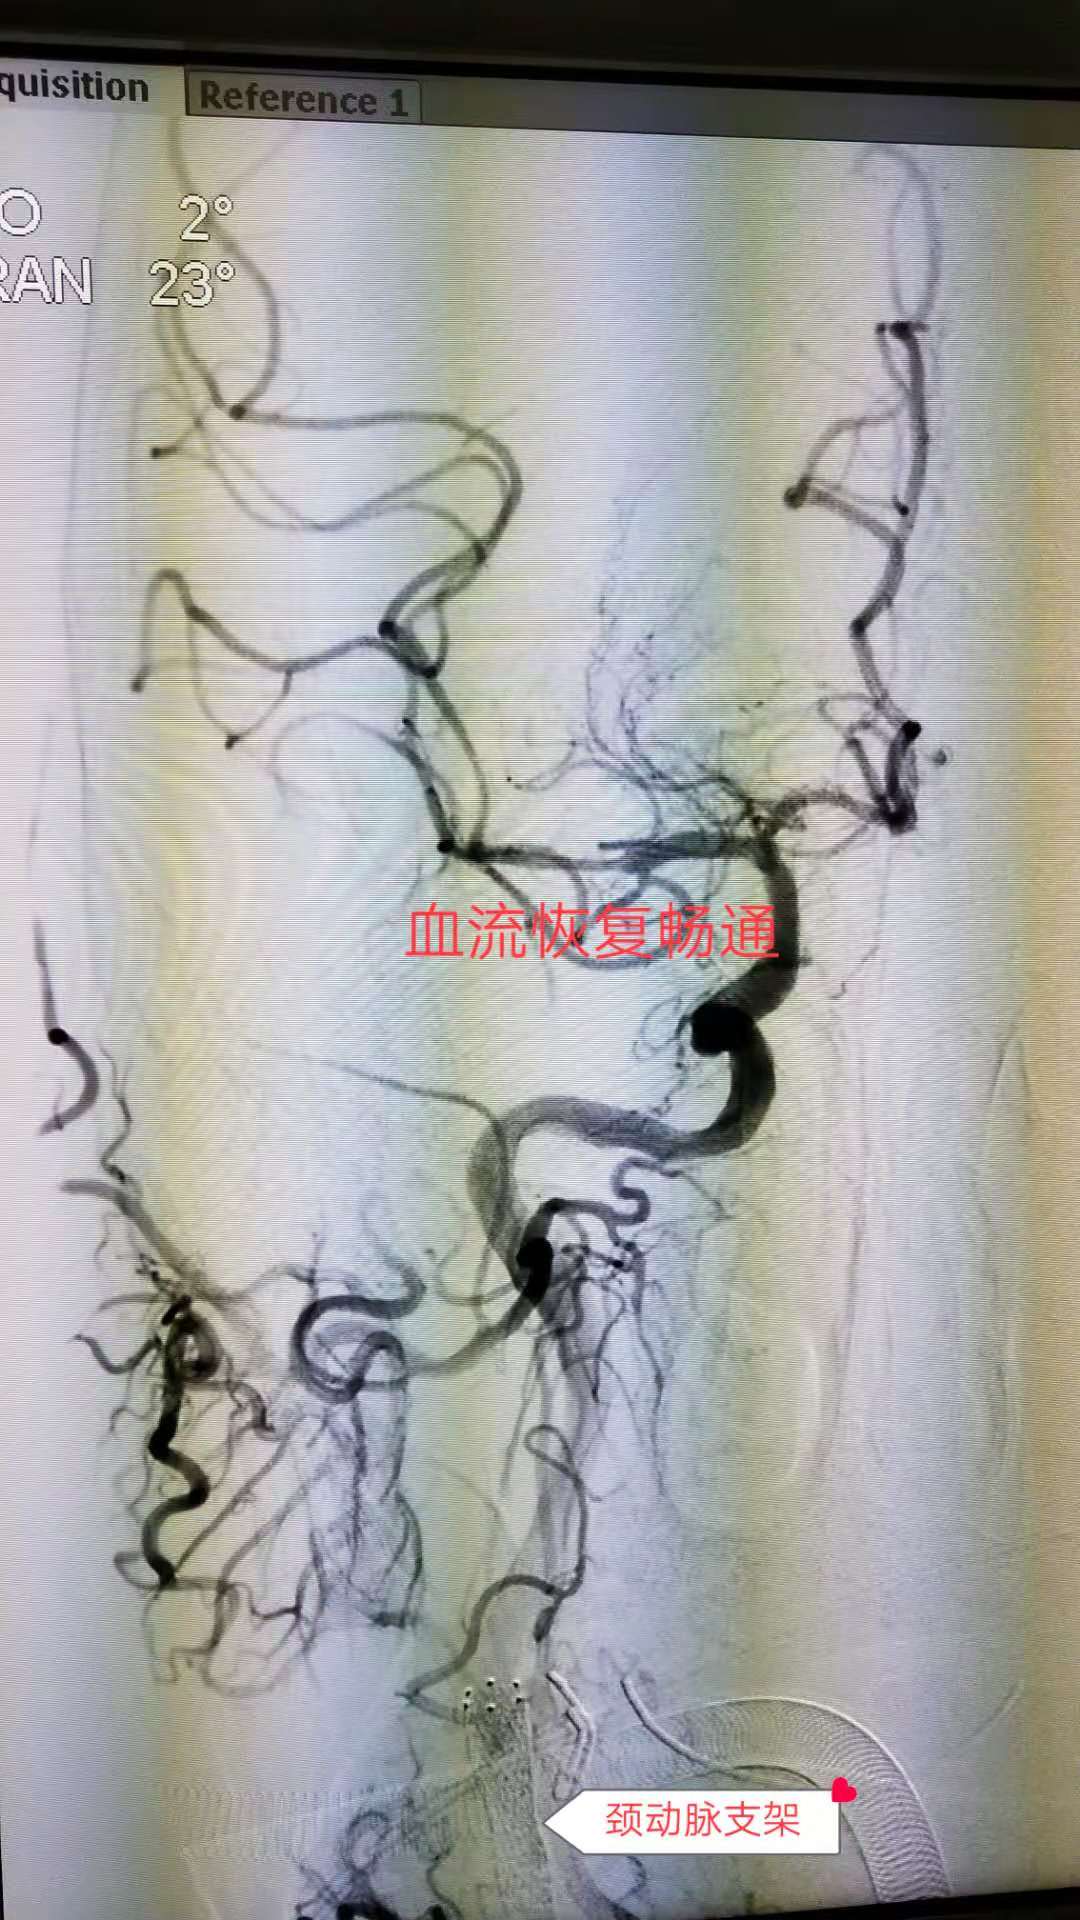

介入血管外科张煜杰主任团队先为患者实施血管造影,明确梗死血管和脑组织范围,造影剂显影显示,该患者右侧颈内动脉开口重度狭窄,颅内段血流缓慢,大脑中动脉堵塞,是一复杂的串联性血管病变。知晓患者病情后,立即为患者实施“颈内动脉支架成型加大脑中动脉取栓术”,先将导丝伸入颈动脉血管,用支架将狭窄处血管撑起来,然后将患者颅内血管的血栓一点点的取出来。

经过2个多小时的共同努力,终于将患者颅血管中内堵塞血栓全部取出,成功开通血管。